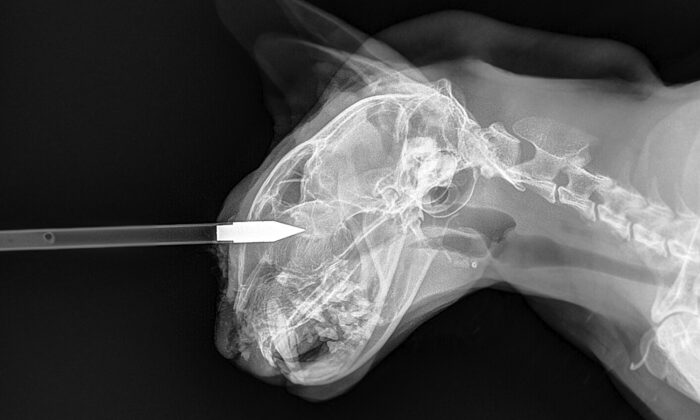

Un homme de Jaipur au Rajasthan, dans le nord de l’Inde, a consacré sa vie à s’occuper des animaux sans défense et sans-abri. Sa…